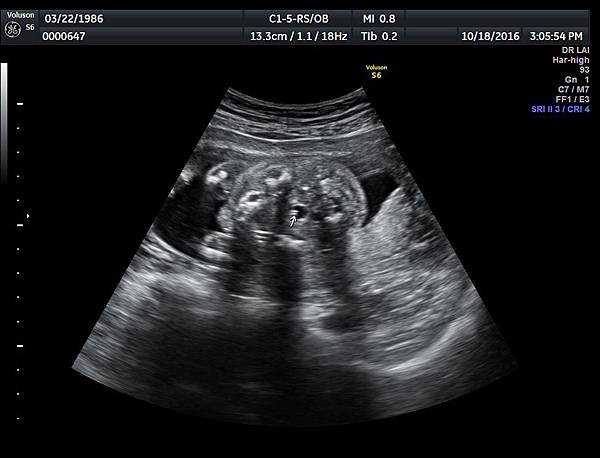

21w 6d right side cleft lip and palate and cleft uvula and brain anomaly < ACC and lissencephaly> images 3421

一個檢查如果要花很長的時間才能完成,這樣的檢查無法變成常規的篩檢方式,我已經在我的診所執行懸雍垂檢查一段時間,我檢查懸雍垂大約30 秒,前提是胎兒的臉最佳位置是側躺,其次是側躺偏向上,我的檢查步驟是上顎(含日後大門牙長出的位置)、舌頭、懸雍垂(= equal sign)(附圖1~8),如果超過60秒無法完成,只有兩個原因,一個是胎兒姿勢不適合或喉嚨羊水空間太小,這時候不要硬碰硬,只要先檢查其他部位,等待時機再回來即可,我的經驗是90%的cases都能順利完成這項檢查(肚皮厚的case真的是很難)。